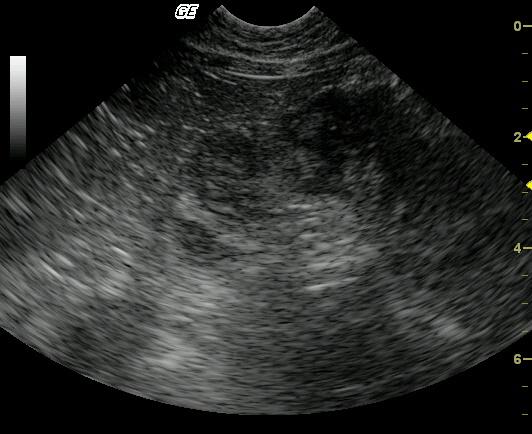

This image shows marked, circumferential, slightly asymmetrical, focal bowel wall thickening. The affected bowel wall is hypoechoic, heteroechoic, lacks layering, and possesses a slightly undulating serosal margin. The peri-intestinal mesentery and omentum are echogenic, most notably within the far field.

Differential diagnoses included an intestinal wall mass with suspicion of multifocal ulceration and peri-intestinal inflammation. Partial omental and/or mesenteric adhesion cannot be definitively ruled out. These findings would be most consistent with neoplasia. Inflammatory or granulomatous diseases were considered less likely.